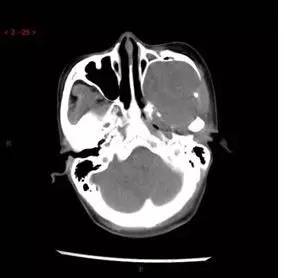

CT平扫轴位

解析:本病例为中颅窝至颞下窝沟通性病变,对周围骨质主要呈膨胀压迫性改变,伴囊变、出血。